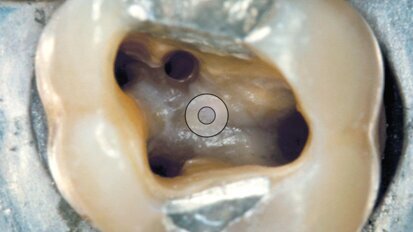

Le nuove punte da ultrasuoni per la rifinitura della cavità d’accesso A-C Tips

Gli ultrasuoni si sono rivelati in endodonzia nettamente superiori alle frese montate su manipoli ad alta o a bassa velocità. L’efficienza nel taglio che...